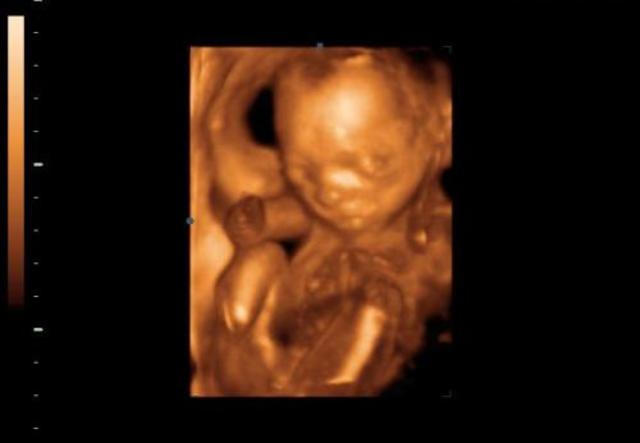

• A magzat fejlődése a negyedik hónapban

A magzat fejlődése a negyedik hónapban

A negyedik hónapban baba már folyamatos mozgásban van, csontjai pedig egyre szilárdabbak, így egyre nagyobb az esély, hogy édesanyja is megérezze az apró rúgásokat.